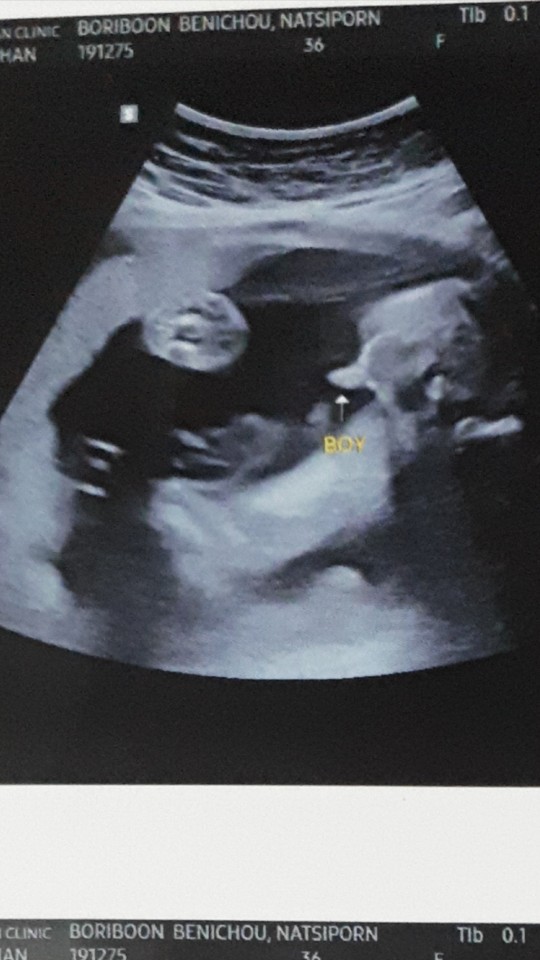

บ้านนี้มาเป็นแท่งเลยค่ะ 😄😊

ทั้งพวงทั้งแท่งเลยคร้าบ 😊😁

คุณหมอบอกผู้ชาย100%คร้าบบบ😂😂